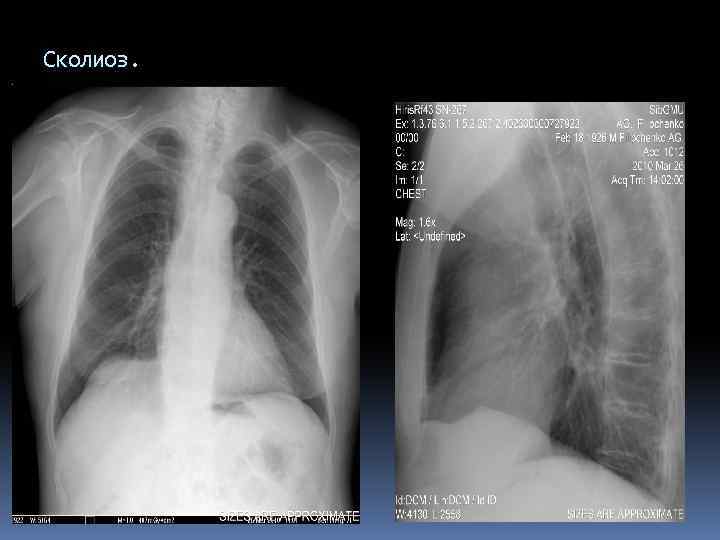

Сколиоз.